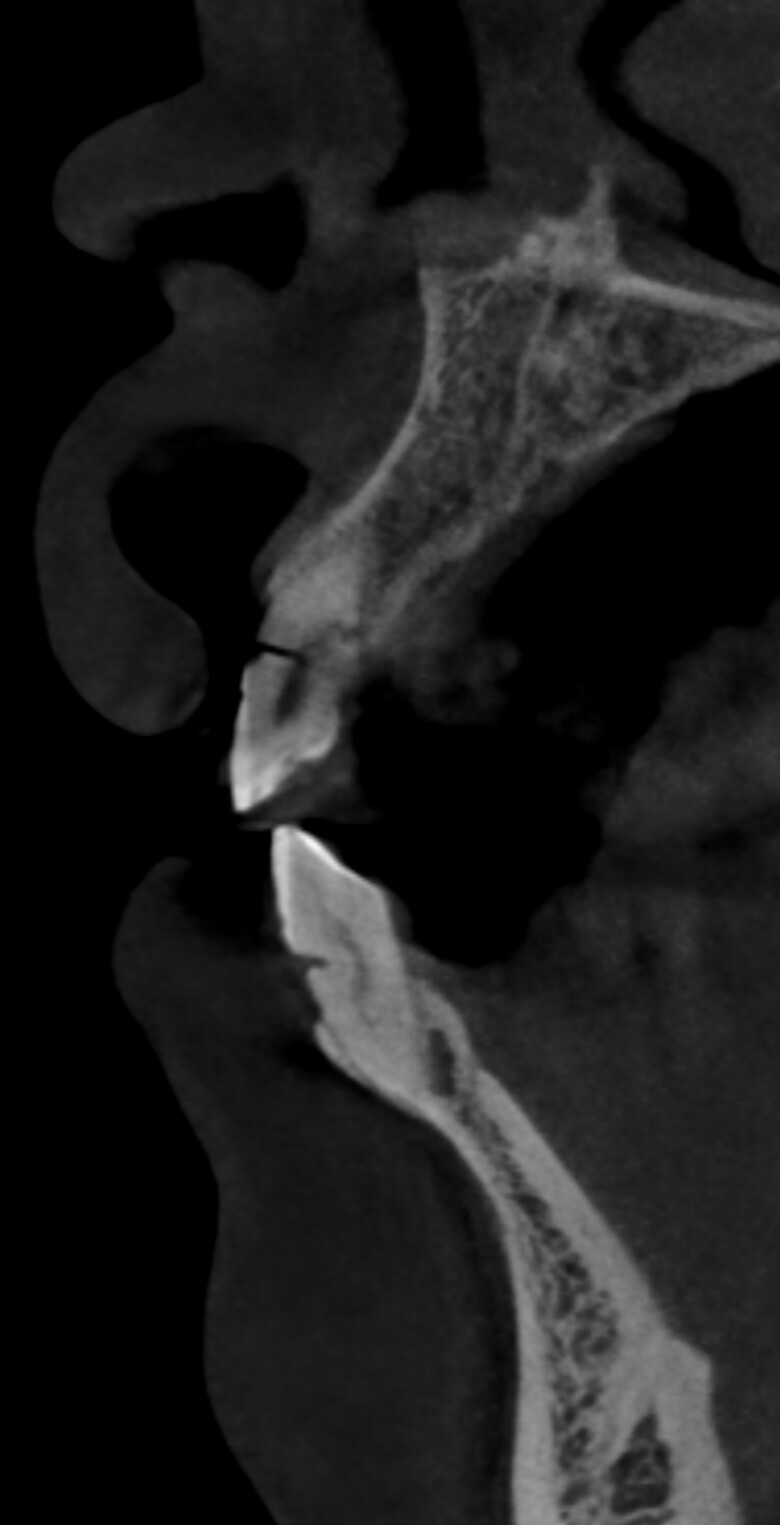

Implants placed too close: Is this restorable?

I am feeling really humble. I’ve placed multiple implants and thinking this should be a straightforward case. I was wrong. I know it’s poorly planned and freehand did not go well. Are these restorable? Should I explant and redo? If I do remove these, how easy is it to remove these?